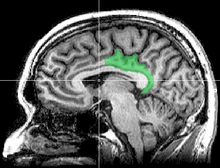

![]() Medial surface of left cerebral hemisphere. | |

The posterior cingulate cortex (PCC) is the backmost part of the cingulate cortex, lying behind the anterior cingulate cortex. This is the upper part of the "limbic lobe". The cingulate cortex is made up of an area around the midline of the brain. Surrounding areas include the retrosplenial cortex and the precuneus.

Cytoarchitectonically the posterior cingulate cortex is associated with Brodmann areas 23 and 31.